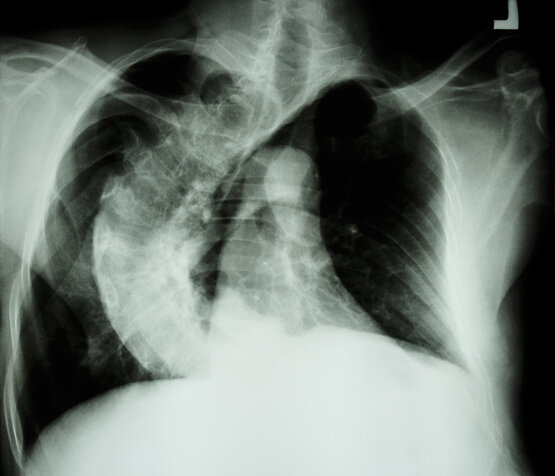

Der Schweregrad der Fehlstellung wird dabei anhand eines Röntgenbildes in Abhängigkeit des gemessenen Cobb-Winkels und der Seitabweichung der Wirbelsäule zum Beckenzentrum (Lotdeviation) beurteilt.

Die Behandlung der idiopathischen Skoliose nach Feststellung der Diagnose, richtet sich dabei nach dem noch zu erwartenden Längenwachstum der Wirbelsäule, welches sich auch mithilfe von Röntgenaufnahmen des Beckenkamms oder der Handwurzelknochen prognostizieren lässt (Risser-Stadium, Sanders-Stadium).

Die davon Betroffenen haben durch Ausbildung von keilförmigen Wirbeln während des Längenwachstums eine oft schmerzhafte und sehr früh wackelsteife Verkrümmung der Wirbelsäule. Der Schweregrad der Verkrümmung kann auch hier im Röntgenbild nach dem seitlichen Cobb-Winkel oder dem Stagnara-Winkel gemessen und beurteilt werden.